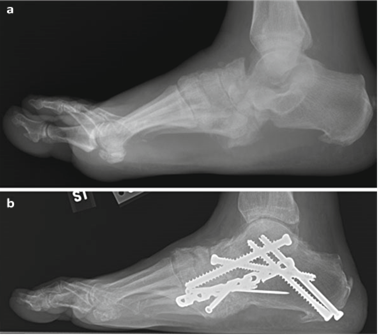

Weight-bearing anteroposterior (AP), lateral, and sesamoid axial radiographs are mandatory. On the AP view, the surgeon measures the Hallux Valgus Angle (HVA, normal < 15°), the Intermetatarsal Angle (IMA, normal < 9°), and the Distal Metatarsal Articular Angle (DMAA). The lateral view is scrutinized for Meary's angle (talo-first metatarsal angle) to identify midfoot collapse, as well as the presence of dorsal osteophytes indicative of hallux rigidus. The sesamoid axial view is critical for assessing the degree of sesamoid subluxation and the integrity of the crista.

To achieve multiplanar correction, the surgeon must address the sagittal, coronal, and transverse planes. The first metatarsal is plantarflexed to restore the longitudinal arch, rotated out of pronation to realign the sesamoids, and translated laterally to close the IMA. Subchondral drilling or feathering is performed to optimize the biological environment for fusion. Fixation is traditionally achieved with two or three crossed solid or cannulated screws (typically 3.5mm or 4.0mm). Recently, plantar or medial locking plates have gained immense popularity due to their superior biomechanical construct, allowing for earlier weight-bearing. Bone graft or orthobiologics may be packed into the arthrodesis site to stimulate osteogenesis.

| Nonunion (Lapidus/MTP) | 3 - 10% | Inadequate cartilage resection; Poor fixation construct; Patient non-compliance; Smoking. | Revision arthrodesis with structural bone grafting and robust locking plate fixation. |

| Transfer Metatarsalgia | 5 - 15% | Excessive shortening or dorsal elevation of the first metatarsal (malunion). | Orthotic management (metatarsal pads); Weil osteotomies of lesser metatarsals; Plantarflexing 1st TMT revision. |